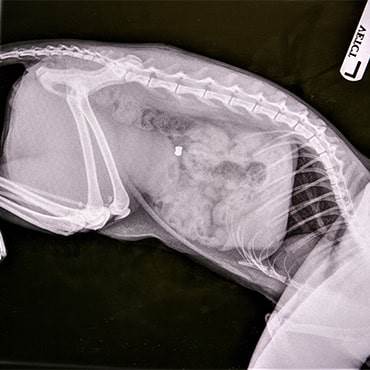

Eve rushed Stovie to Basildon PDSA Pet Hospital where x-rays confirmed her worst fears: her beloved cat had been shot with an airgun and the pellet was lodged inside his tummy.

PDSA Vet Hannah Johnston said: “Stovie needed immediate treatment to surgically remove an airgun pellet lodged in his tummy. We flushed his abdomen and thoroughly checked to make sure that his intestines had not been damaged. It’s amazing that the pellet did not cause further damage - luckily Eve spotted the wound and brought him in when she did. He was incredibly lucky.”